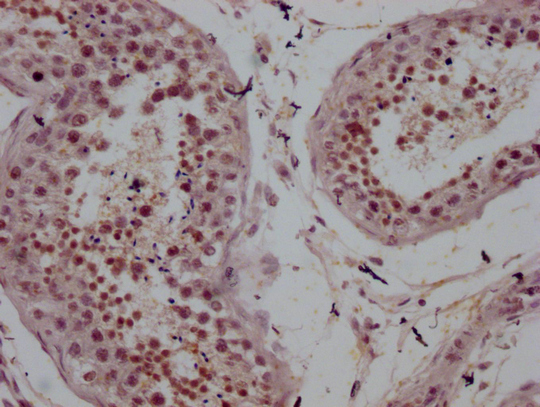

Human heart tissue

1:100